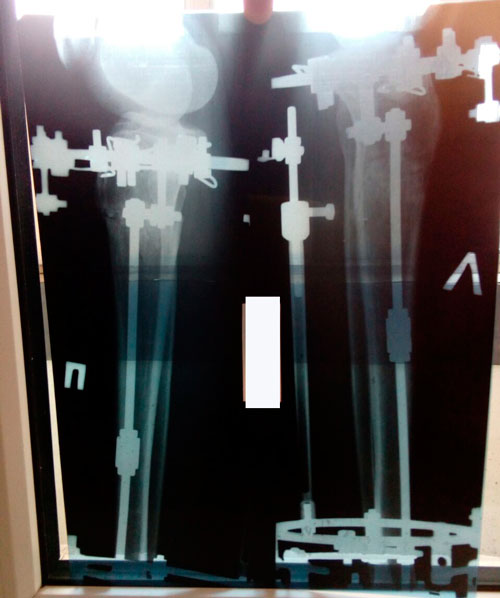

Ножки рентген в 90 дней.